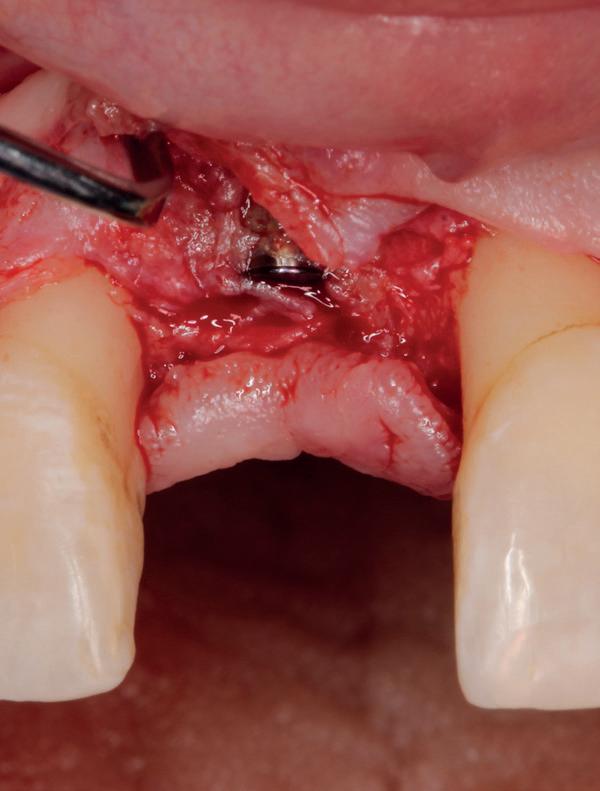

Implantologische behandelingen in het esthetische front vragen meer dan technische vaardigheid alleen. Ze vragen om overzicht, timing, vertrouwen en een team dat als vanzelf samenwerkt onder druk. Juist bij complexe casussen, waarin angst, infectie en hoge esthetische verwachtingen samenkomen, wordt zichtbaar hoe bepalend de rol van de tandartsassistent is.

Deze casus beschrijft een uitgebreide immediate implantaatbehandeling bij een patiënt die door meerdere collega’s werd geweigerd. Niet omdat de mogelijkheden ontbraken, maar omdat de complexiteit vroeg om een perfect afgestemde samenwerking. Het verhaal laat zien hoe de assistent in zo’n traject veel meer is dan een uitvoerende kracht of “mal”, maar een dynamische surgical guide die het proces mede stuurt, bewaakt en mogelijk maakt.De patiënt: wanneer alles samenkomt

Ze kwam binnen op een dinsdagochtend, iets voor achten. Een vrouw van begin zeventig, met een zachte stem en ogen die meer vertelden dan haar woorden. Ze vertelde dat ze een eigen B&B had en dat ze zich nauwelijks kon voorstellen gasten te ontvangen zonder tanden. Op dit moment kon ze echter nauwelijks lachen. “Het doet pijn… en het ruikt soms ook niet goed,” zei ze bijna verontschuldigend. Haar oude bovenbrug, die ze al meer dan twintig jaar droeg, was langzaam maar zeker ingestort. Er was sprake van cariës onder meerdere pijlers, pusafvloed,

chronische ontsteking en een brug die mobiel was en elke beet pijnlijk maakte. Ze had inmiddels meerdere tandartsen bezocht. Drie hadden haar geweigerd. Te complex. Te veel wensen. Te onvoorspelbaar.

De kern van haar vraag was eenvoudig en tegelijkertijd uitdagend: Is het mogelijk om mijn huidige brug te dupliceren en een nieuwe brug te vervaardigen met minder complicaties?

De basis van een complexe beslissing

Mijn behandelplan begint altijd met een uitgebreid klinisch onderzoek. Dat omvat een medische anamnese, intra- en extra-orale camerafoto’s en uitgebreid verwachtingsmanagement. In deze fase is mijn assistent vooral bezig met het zorgvuldig vastleggen van alle gegevens. Juist dat nauwkeurig documenteren zorgt voor rust in de behandelkamer. Minstens zo belangrijk is het luisteren naar de patiënt. Niet alleen naar de klachten, maar naar het

Na het klinische onderzoek volgde het röntgenologisch traject. De CBCT liet precies zien wat we al vreesden: een front waarin het bot onregelmatig was, duidelijke radiolucenties rond de pijlers en een infectiegebied dat zich onder vrijwel de gehele brug had verspreid. Tegelijkertijd was er ook potentie. Net voldoende botstructuur om immediate implantaatplaatsing te overwegen, mits alles perfect gepland zou worden.